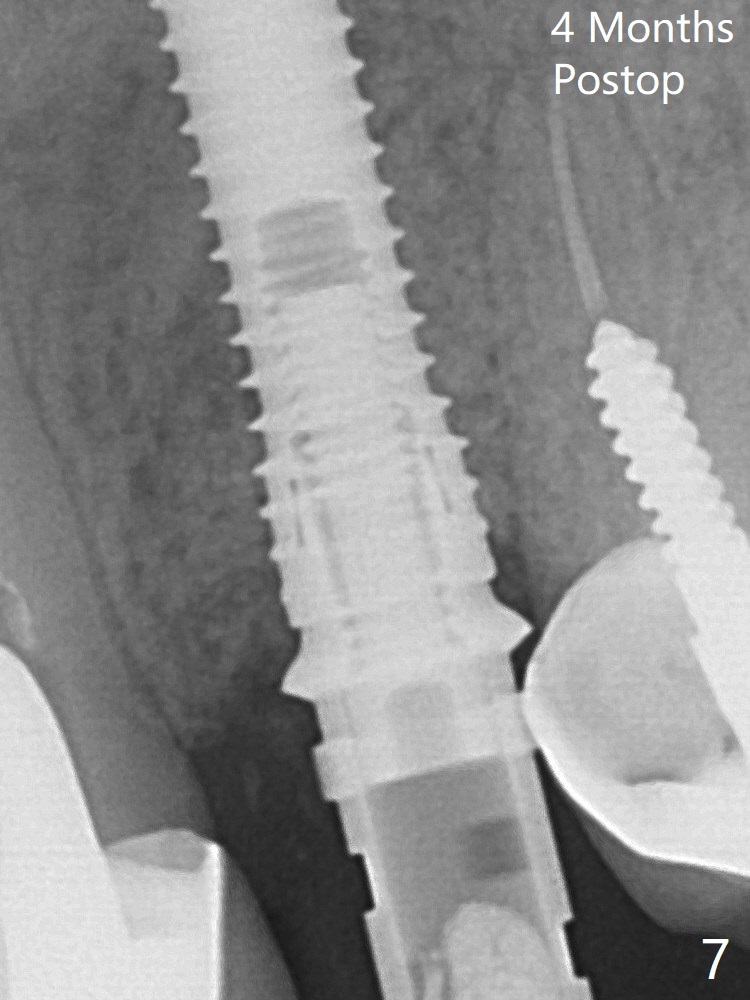

In spite of severe apical infection (Fig1,2 *), a thin narrow strip of the buccal plate (arrowheads, corresponding to the keratinized gingiva) is present when the tooth #11 is extracted.  The thin bone keeps the bulging alveolus, i.e., reservoir for bone graft (Vanilla/Osteogen Fig.4 *) after placement of a 3.8x16 mm implant (Fig.3,4).  A 4.5x1 mm temporary abutment, placed and trimmed for an immediate provisional, seems to be short in cuff.  When an implant is placed deep to prevent periimplantitis, the cuff should be longer, i.e., 3 mm.  X-ray should be taken for the depth confirmation after temporary abutment placement.  Fig.3: a 2 mm drill in place, 18 mm in bone vs. 16 mm of implant placed ~ 2 mm subcrestal (Fig.4).  A narrow implant (3.8 mm) is chosen over 4.5 mm because of the extensive buccal plate defect.  While the hard tissue around the implant seems to be healthy 5 months postop (Fig.7), the soft tissue is not (Fig.8).